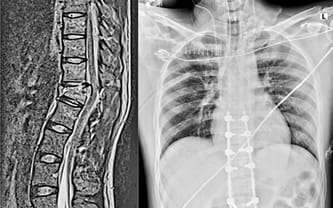

August 16, 2023, is the worst date in our lives. That day, Kacper fell from 5 meters, suffering from multiple injuries, including Th10 and Th12 spinal fractures and paralysis of the lower limbs. An energetic man of many hobbies became a hospital patient fighting for life and health.

He underwent a spine surgery that lasted for hours. After the procedure, he was put in a medically induced coma and on a ventilator for several days. He had breathing difficulties, pulmonary edema, broken ribs and sternum. It wasn't until his condition became fair that he was transferred to the rehabilitation clinic, where he's been staying until today.